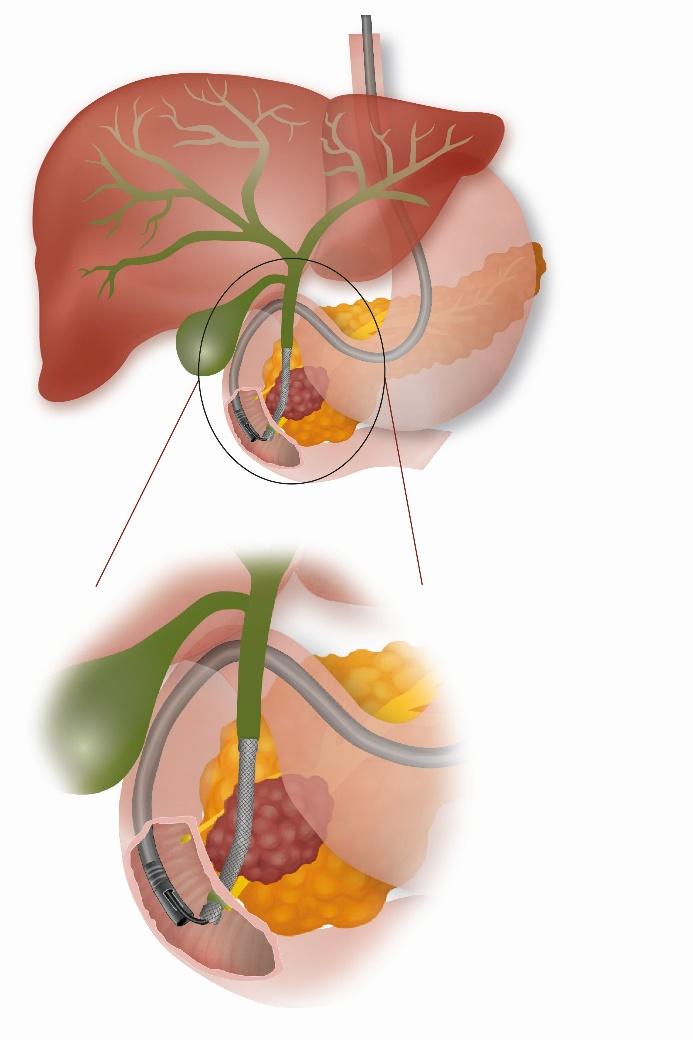

EUS-CDS is een nieuwe techniek die is ontwikkeld om de procedure makkelijker te maken. De endoscoop wordt minder diep in de dunne darm geplaatst waarna de galweg wordt opgezocht met een echo-apparaatje wat op de endoscoop zit. Vervolgens wordt er een gaatje gebrand in de wand van de dunne darm en de galweg, waarna een stent kan worden geplaatst. Zodoende is er een nieuwe verbinding gemaakt tussen de galweg en de dunne darm waardoor de gal kan afvloeien (figuur 2).

Figuur 2. EUS-CDS